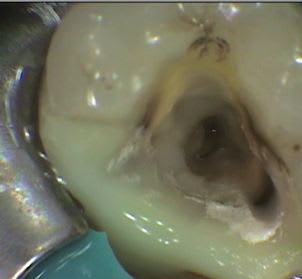

Endo 37 canal secondaire vers espace interradiculaire?

exemple bis